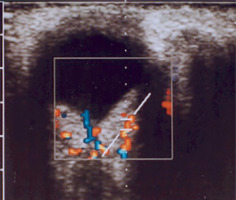

It is a very rare disease, affecting an estimated one in 30,000–40,000 individuals, with around 1,000 cases reported in Poland. The condition is inherited in an autosomal dominant manner. The syndrome is caused by constitutional mutations of the VHL tumor suppressor gene located on the short arm of chromosome 3. Constitutional mutations affecting a single gene are present in all cells of the body and represent the primary cause of pathology in this type of genetic disorder. The syndrome is characterized by the presence of hemangioblastoma-type tumors in the cerebellum, spinal cord, brain, visceral organs, and the eye [16]. The tumors consist of components of hemangioblastomas [6]. Visceral abnormalities are associated with the presence of pancreatic and renal cysts, as well as polycythemia. Tumors such as pheochromocytoma and adenocarcinoma may also occur. Hemangioblastomas that develop in the brain and spinal cord can cause headaches, vomiting, weakness, and loss of muscle coordination (ataxia). Within the ocular globe, capillary malformations affecting the optic nerve and retina are detected. The malformations appear as tumors in both eyes, located peripherally and centrally [6] (Figure 8A, B). Peripheral distribution is characterized by the presence of tortuous, dilated vessels that supply and drain blood from the tumor. In contrast, centrally located vascular tumors typically exhibit an endophytic growth pattern and lack afferent and efferent vessels associated with vascular malformations. Disease progression may lead to retinitis and retinal detachment, iridocyclitis, and rubeosis iridis. The changes may result in the development of secondary glaucoma.

The diagnosis of phakomatosis is based on a thorough medical history, which includes the presence of phakomatosis-type lesions or other systemic disorders in the family, as well as symptoms reported by the child or their parents. Ophthalmologic examination includes all elements of the clinical assessment, performed under local or general anesthesia, depending on the child’s age. Important diagnostic tests include genetic analyses [17]. Prenatal diagnosis is possible through molecular testing of amniotic or chorionic cells. Genetic counselling plays a crucial role in supporting informed reproductive decision-making for patients and at-risk family members [18, 19]. Imaging examinations are also important in the diagnostic work-up. These include magnetic resonance imaging (MRI) and computed tomography (CT) of organs and systems potentially affected by the disease process – such as the head and brain – as well as ocular and orbital ultrasound, chest X-ray, electrocardiography (ECG), electroencephalography (EEG), and other examinations required for an accurate diagnosis. An essential part of diagnosis and therapy involves consultations from other medical specialties and interdisciplinary collaboration.